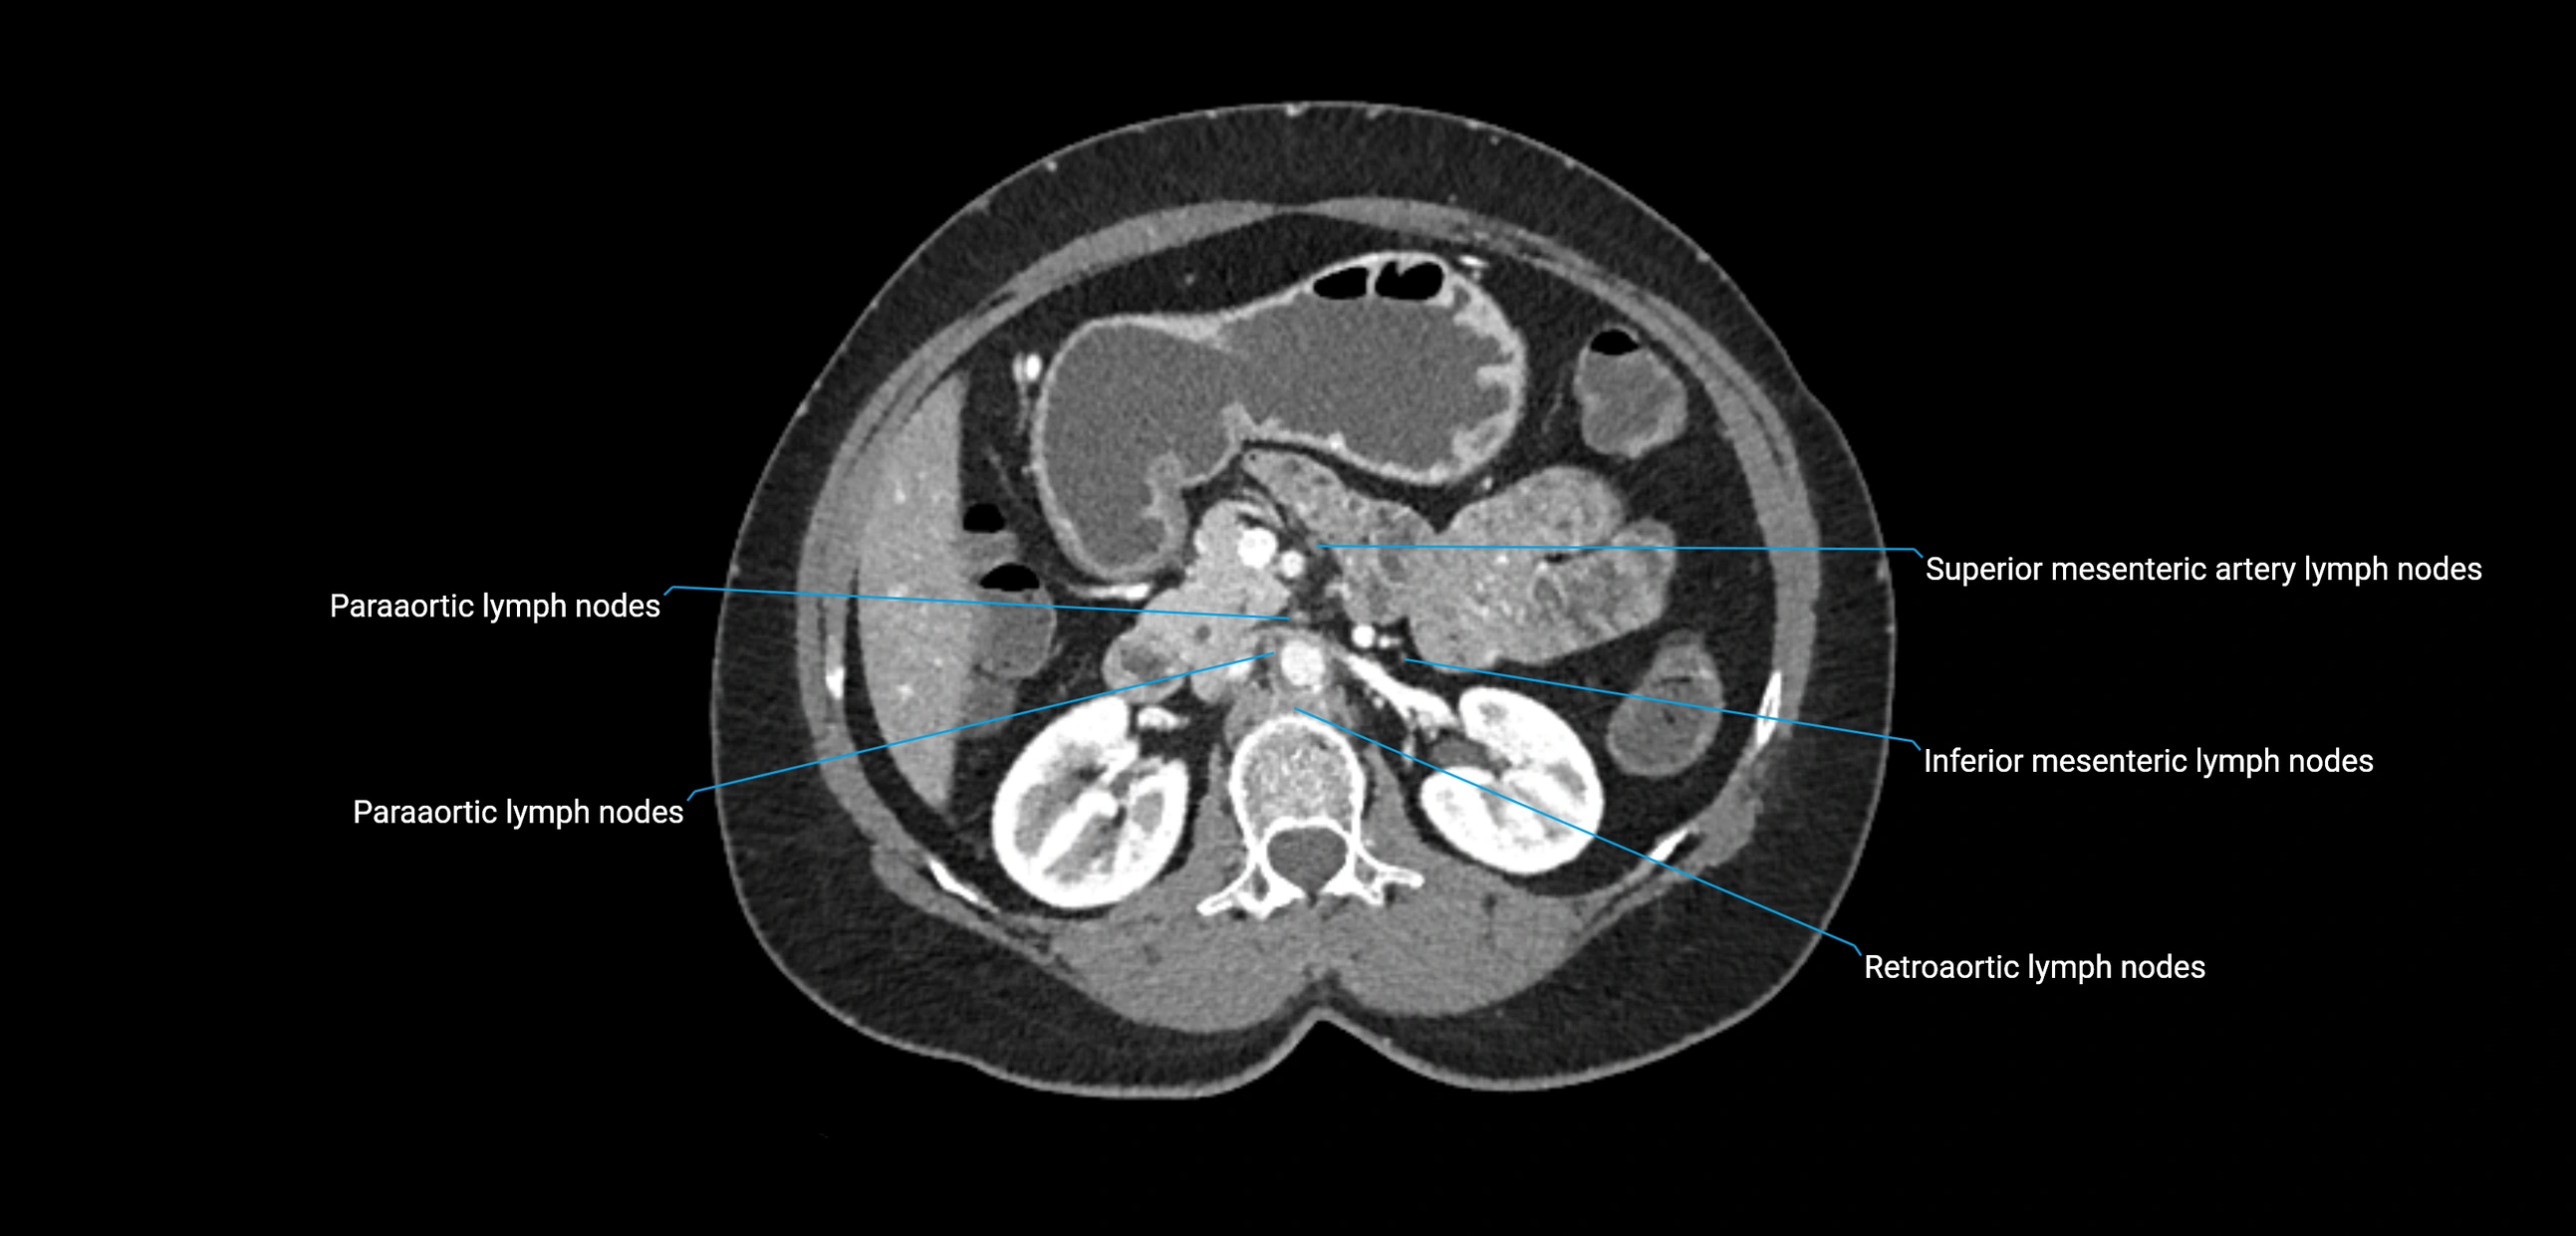

The lateral aortic lymph nodes (also called para-aortic lymph nodes) are a major group of retroperitoneal lymph nodes located along the abdominal aorta and its branches. They lie between the diaphragmatic crura superiorly and the bifurcation of the aorta at L4 inferiorly.

They are positioned on both sides of the abdominal aorta:

• Right lateral aortic nodes: adjacent to the inferior vena cava (IVC)

• Left lateral aortic nodes: lateral to the abdominal aorta

These nodes receive lymph from a wide range of abdominal and pelvic structures. Specifically, they drain lymph from the kidneys, suprarenal glands, gonads (testes/ovaries), uterus, uterine tubes, and pelvic organs, before converging into the lumbar lymphatic trunks, which terminate in the cisterna chyli → thoracic duct.

Clinically, the lateral aortic lymph nodes are critically important in oncology, being involved in the spread of testicular cancer, ovarian cancer, endometrial cancer, cervical cancer, renal malignancies, and retroperitoneal lymphomas. They are also key targets in retroperitoneal lymph node dissection (RPLND) for testicular tumors.

CT Appearance

CT Pre-Contrast:

• Nodes appear as soft-tissue density nodules adjacent to the aorta and IVC

• Calcification may be seen in chronic infections (e.g., tuberculosis)

CT Post-Contrast:

• Normal nodes enhance homogeneously

• Malignant nodes may show heterogeneous enhancement, central necrosis, or conglomerate formation

• Size >1 cm short axis is suspicious, though morphology and distribution are equally important

CT Venography (CTV):

• Demonstrates nodal encasement or compression of adjacent vessels (aorta, IVC, renal veins)

• Useful in staging testicular and ovarian malignancies

• Provides 3D reconstructions for retroperitoneal lymph node dissection planning

CT image

image